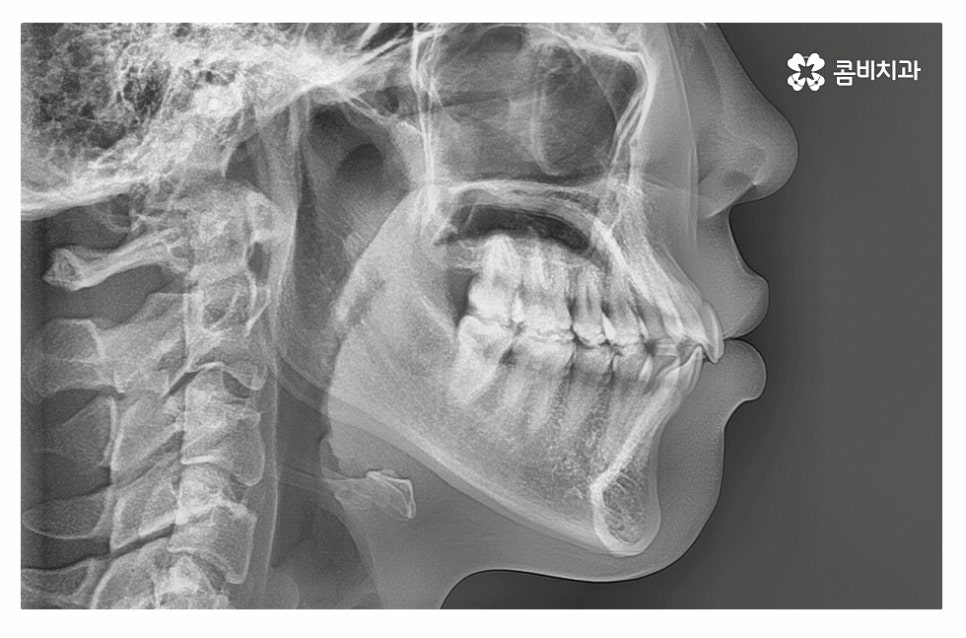

돌출입치아교정 원하시는 분들의 경우 돌출입의 원인에 대해서

정확히 파악을 해야 하기 때문에 정밀검진을 우선 진행해야 하며

치아교정 만으로 치료가 가능한 분들도 있지만 수술이 함께

병행되어야 하는 경우도 있기 때문에 정확한 치료 계획을

세우기 위해서는 1:1로 의사와 정확하게 상담받아야 할 필요가 있어요.

돌출입치아교정은 돌출입의 원인을 정확하게 파악하는 것이 중요한데

일반적으로는 발치를 하는 경우가 많지만 구강구조 및 골격 등은

개인에 따라 다르기 때문에 치간 삭제, 구개확장 장치 등을 활용하여

비발치로도 치아의 이동 공간을 확보하여 비발치치아교정을 하는 사례도 있어요.